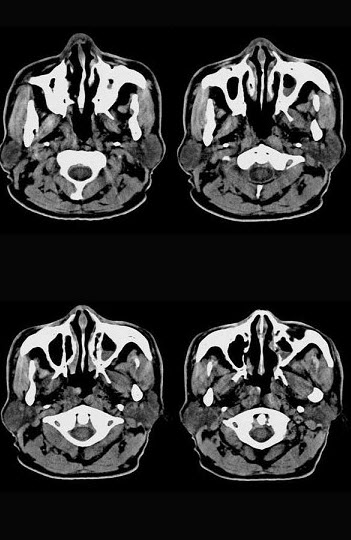

男,61岁,流鼻血三天。如图所示最可能的诊断为()。

A:鼻咽淋巴滤泡增生

B:鼻咽腺样体增生

C:鼻咽纤维血管瘤

D:小唾液腺瘤

E:鼻咽部息肉